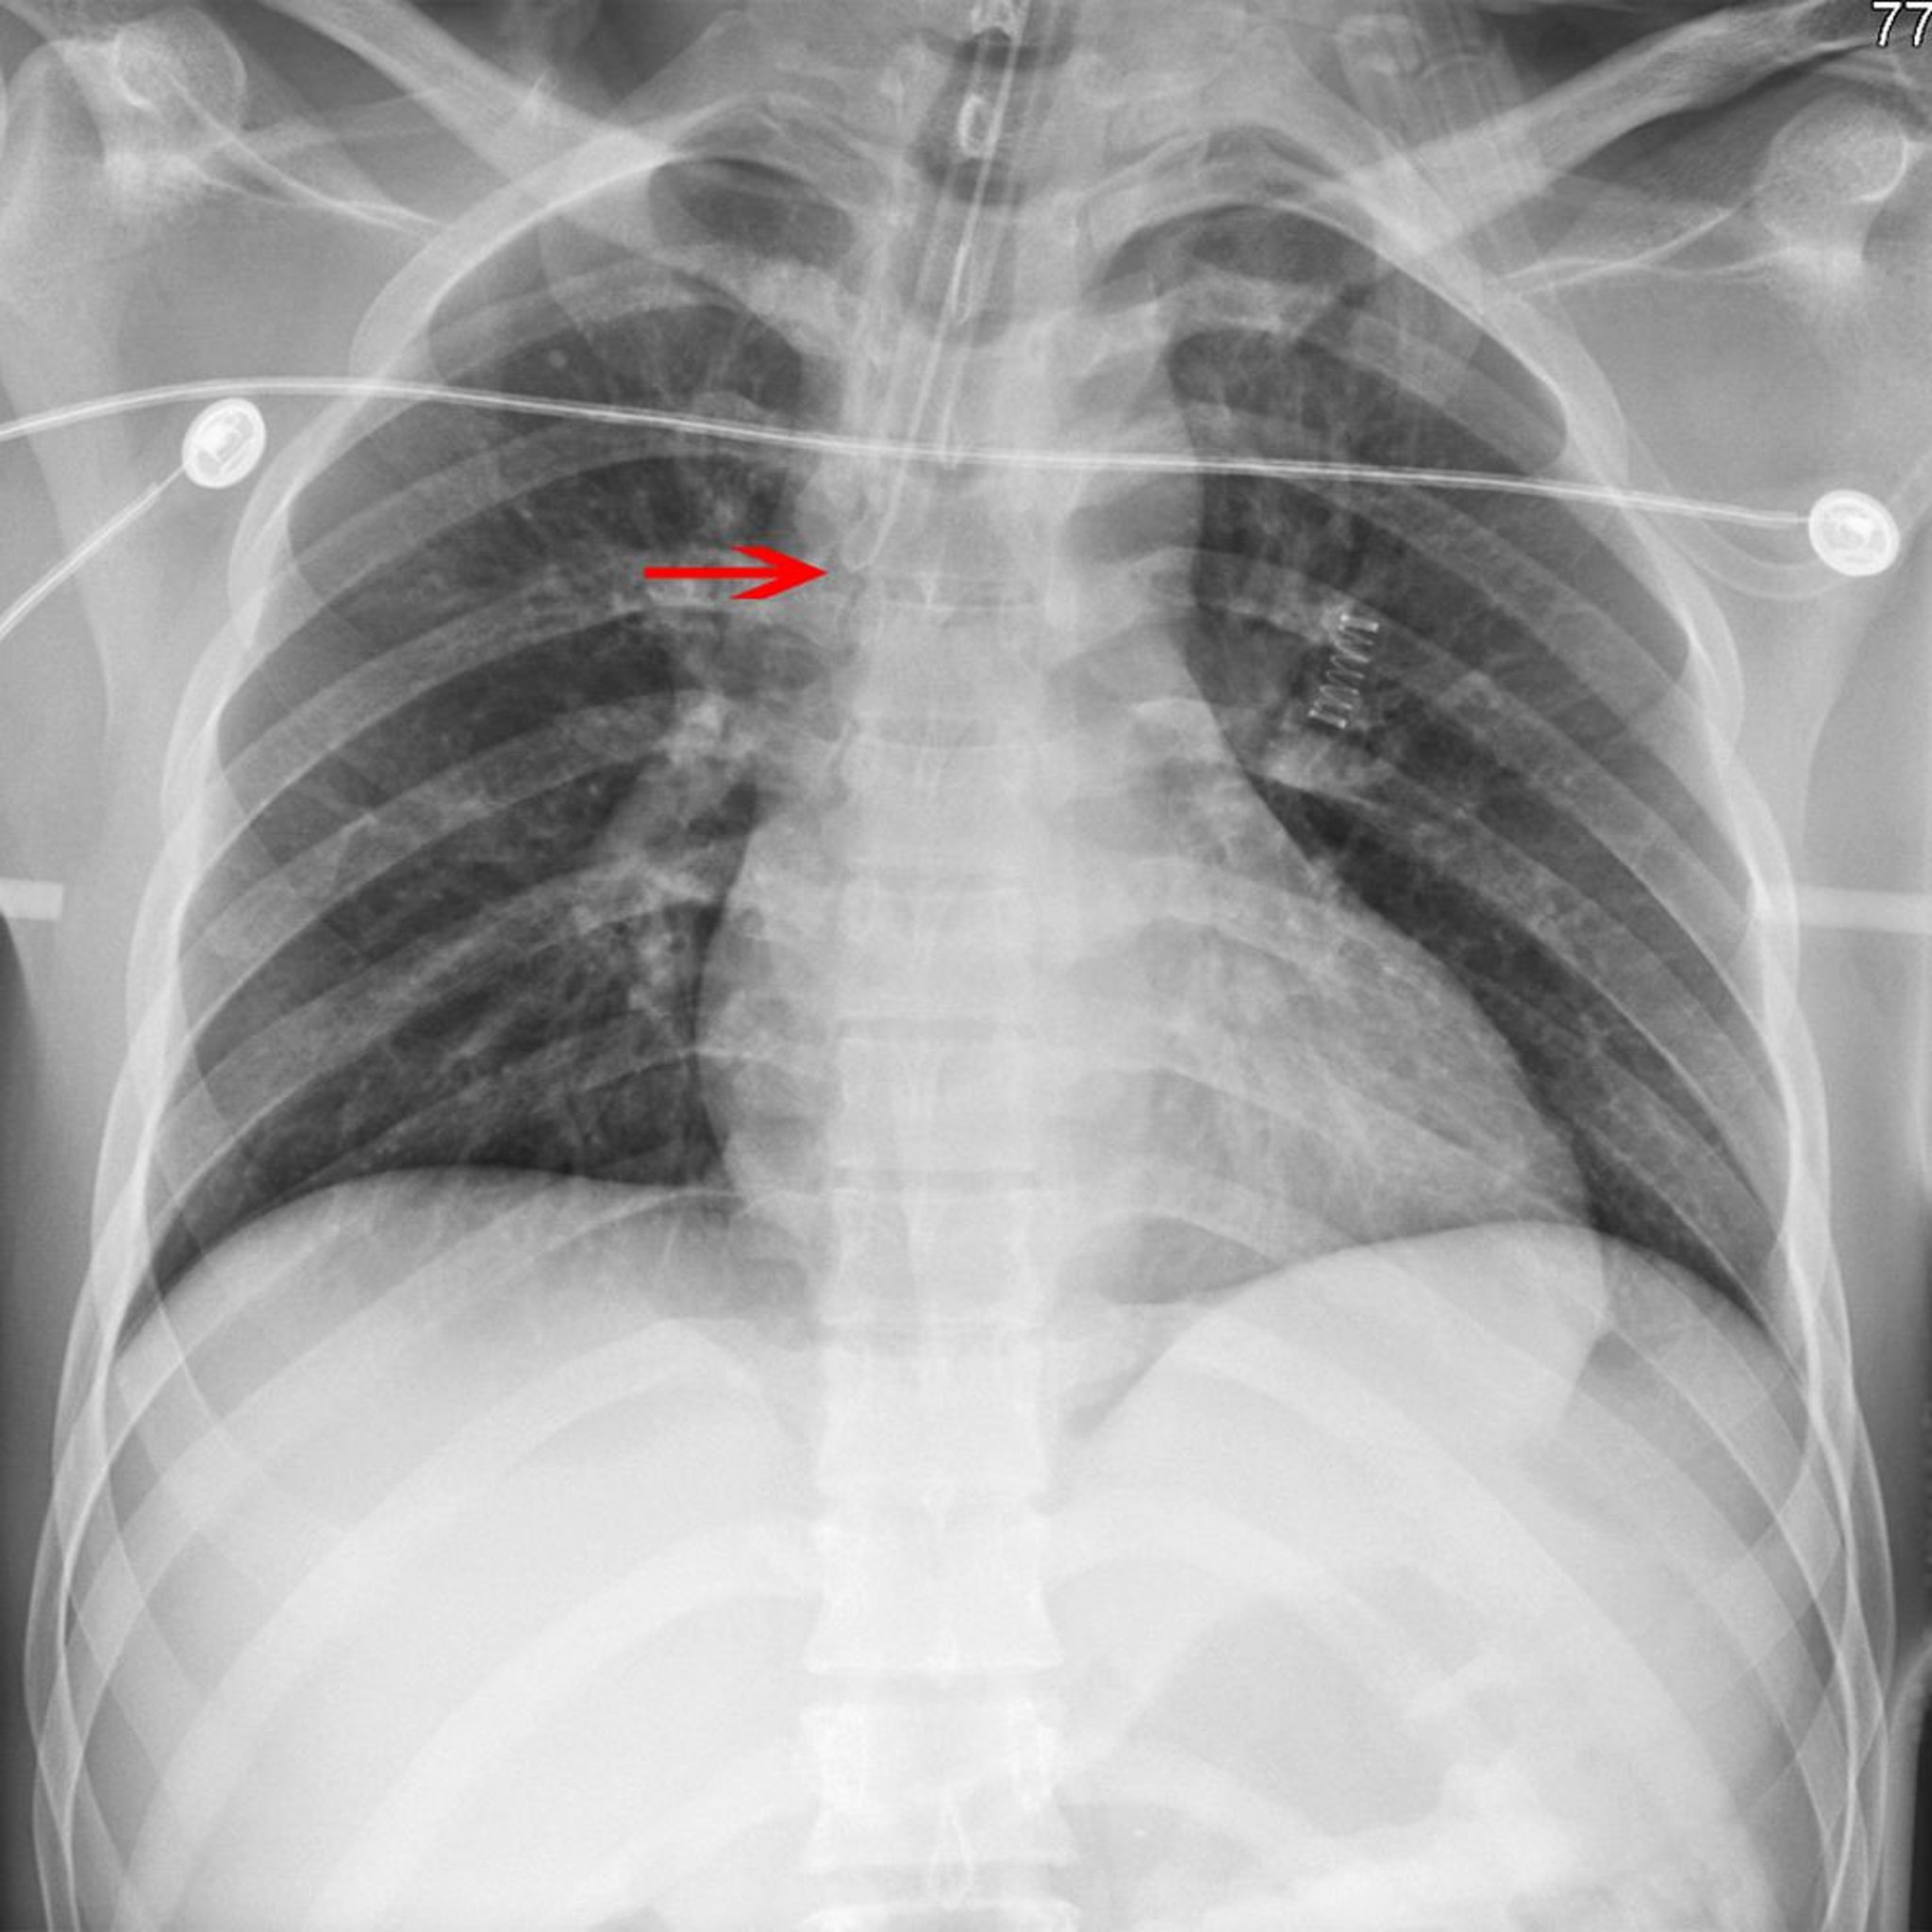

La flecha señala la punta de un tubo endotraqueal colocado incorrectamente en el bronquio principal derecho.